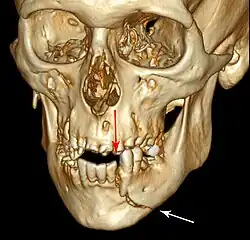

Computed tomography

Computed tomography is the most sensitive and specific of the imaging techniques. The facial bones can be visualized as slices through the skeletal in either the axial, coronal or sagittal planes. Images can be reconstructed into a 3-dimensional view, to give a better sense of the displacement of various fragments. 3D reconstruction, however, can mask smaller fractures owing to volume averaging, scatter artifact and surrounding structures simply blocking the view of underlying areas.

3D computed tomographic image of a mandible fracture in two places. One is a displaced right angle fracture and the other is a left parasymphyseal fracture. | |

3D CT reconstruction of mandible fracture, white arrow marks fracture, red arrow marks moderate displacement and open bite